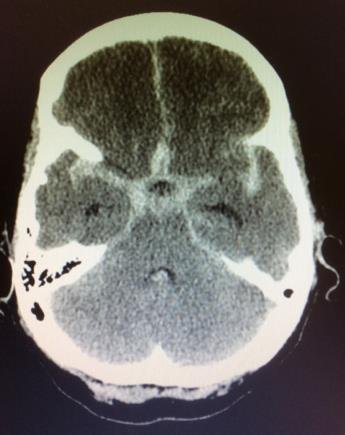

La rotura de un aneurisma cerebral provoca una hemorragia subaracnoidea, caracterizada por el vertido de sangre hacia las cisternas, cisuras y surcos de la base del cerebro, habitualmente ocupados por líquido cefalorraquídeo. En ocasiones, el sangrado puede extenderse al interior del tejido cerebral.

El síntoma principal es una cefalea súbita, muy intensa y de aparición brusca, que puede acompañarse de somnolencia y, en los casos más graves, de pérdida de consciencia. Se trata de una situación clínica extremadamente grave que amenaza la vida del paciente, tanto en el momento del sangrado como durante las semanas posteriores, debido a las posibles complicaciones asociadas.

El TAC craneal es la prueba diagnóstica inicial de elección. El paciente debe ingresar de forma inmediata en una unidad de cuidados intensivos.

En el contexto de una hemorragia subaracnoidea, el diagnóstico del aneurisma cerebral roto suele realizarse mediante angio-TAC craneal, tras la detección inicial del sangrado en el TAC simple.